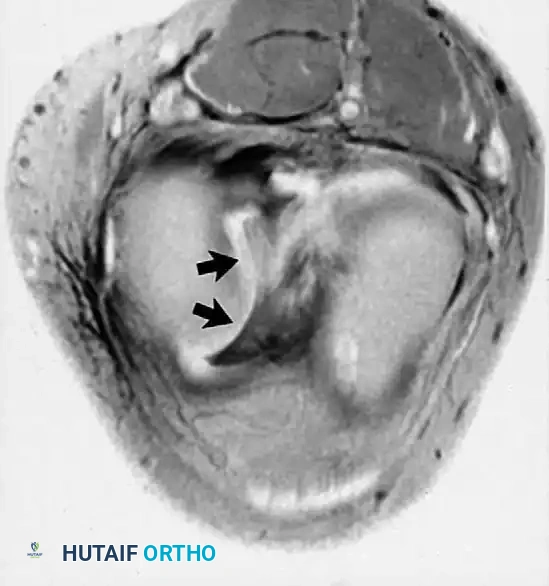

التمزقات المعقدة والمزاحة

بعض التمزقات تكون شديدة لدرجة أن جزءا من الغضروف ينفصل وينزاح من مكانه الأصلي ليستقر في منتصف المفصل، مثل تمزق يد الدلو، مما يسبب انغلاق الركبة الميكانيكي.

في حالات أخرى، قد ينزاح الجزء الممزق إلى الأسفل تحت الأربطة الجانبية.